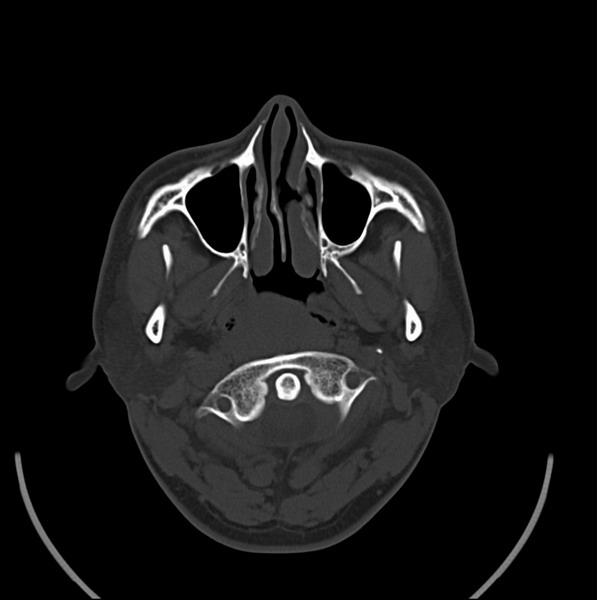

男、30、发现鼻咽部肿瘤侵犯海绵窦,未发现明显淋巴肿。请问国内那家医院治疗鼻咽部肿瘤最好?手术以何种方式为主?病灶可否全部切除?急切期待的大家的帮助。

扫描示鼻咽腔不对称,中度狭窄,右侧咽隐窝消失,局部软组织肿块,鼻咽右侧壁增厚形成肿块,突入鼻咽腔,肿块平扫呈等密度,肿块向深部侵润,右侧翼内外肌受侵,右侧咽旁间隙变窄;向后生长,头长肌界线欠清,向后上生长侵犯同侧颈动脉鞘区。双侧海绵窦增宽,内见软组织影与鼻咽部肿块相连。考虑鼻咽癌。鼻咽癌主要是放射治疗,且效果较好;到当地有治疗设备较大医院治疗即可。